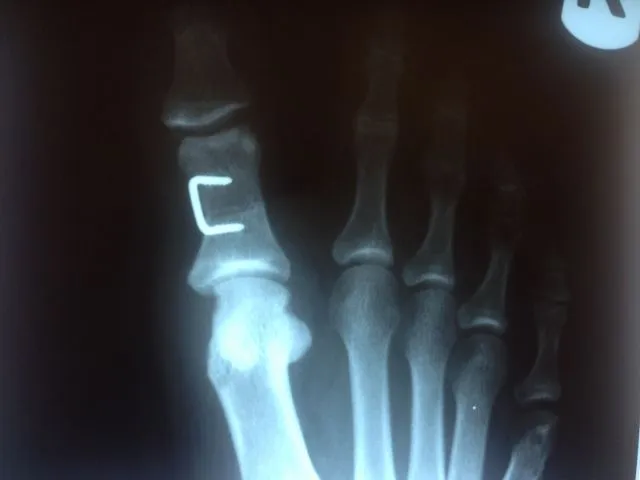

During surgical correction of the bunion a v-shape bone is made in most cases to translate the head of the 1st metatarsal laterally which creates an overhang of bone from the previous position of the bone (pictured left). The overhang is remove and the new position of the bone is held with some type of fixation which varies from screws, staples, or pins which is the case here. The pin is buried left in permanently (pictured right).